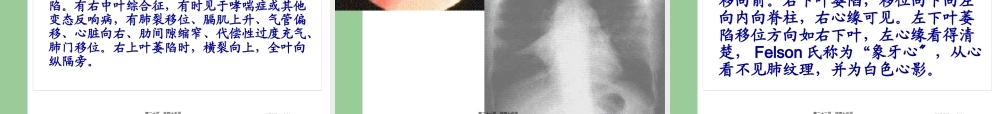

外科胸部X线片系统读片方法介绍Sheldon教授的24个字母〔A-X〕系统读片法,可以减少漏诊。517健康网517jkw.org第一页,共四十五页。胸部X线片系统读片原理A〔Airway〕气道在胸上部,看它是否居中,脊柱是否直线经过,气管有无移位,有无纤维组织牵拉使肺容积缩牵、过度充气及压迫。有无支气管气管巨大症,肺叶开口压迫、狭窄、隆突受压等支气管肺癌征象。517健康网517jkw.org第二页,共四十五页。胸部X线片系统读片原理B〔Bone〕肋骨距是否某侧缩窄,肋骨有无缺损,如第一肋骨上缘缺损,有硬皮病、类风湿性关节炎的可能。第7~9肋骨下缘缺损示主动脉狭窄,见于儿童先天心脏病;法乐氏四联症可见左肋下缘缺损。咳嗽所致骨折,可见于6~9肋,第7肋腋后线可见叉形肋。鸽胸与先天性房室间隔缺损相关,也见于儿童哮喘症或脊柱侧凸严重时伴通气功能降低者。骨脱钙可见于类固醇治疗患者、老年、肾病、或其他代谢病者。517健康网517jkw.org第三页,共四十五页。胸部X线片系统读片原理C(Cor)心脏右缘有两弓,左缘有四弓。右两弓消失见于漏斗胸、右中叶萎缩、肺炎。形状变化或心脏扩大,见于先天性心脏病、心力衰竭。517健康网517jkw.org第四页,共四十五页。517健康网517jkw.org第五页,共四十五页。上腔静脉右心房主动脉弓肺动脉段左心耳左心室517健康网517jkw.org第六页,共四十五页。胸部X线片系统读片原理D〔Diaphragm〕膈肌右高于左半个肋间隙,一侧高,考虑胸部肿瘤、纤维组织牵拉、膈下脓肿。半侧膈肌升高考虑外伤、中风、颈部感染或肿瘤、肺炎或放射治疗后。右侧可见膈肌伴弯刀征。517健康网517jkw.org第七页,共四十五页。胸部X线片系统读片原理E〔Esophagus〕食管位于气管右,假设有空气液面,考虑食管不能松驰或狭窄。517健康网517jkw.org第八页,共四十五页。胸部X线片系统读片原理F〔Fissures〕肺裂将各肺分为各叶,左右各有一斜裂,右侧有横裂,斜裂下端止于膈肌,决不止于前胸壁,有异常时示有病变。517健康网517jkw.org第九页,共四十五页。517健康网517jkw.org第十页,共四十五页。胸部X线片系统读片原理G〔Gastricbubble〕胃泡在左侧,假设在右,考虑内脏转位,胃泡不见,考虑食管不能松驰。胃泡在心右可能为膈疝。517健康网517jkw.org第十一页,共四十五页。517健康网517jkw.org第十二页,共四十五页。胸部X线片系统读片原理H〔Hila〕肺门移位示肺局部萎缩、过度充气等,肺门区扩大可能是肺癌转移、肺内感染、免疫疾病或结节...